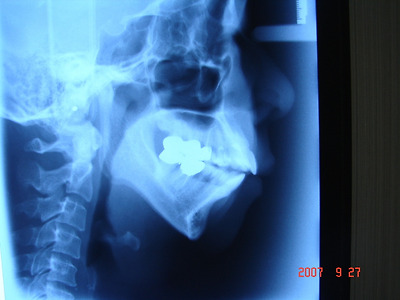

무턱 상태- 수술전 엑스레이와   턱끝 절골 수술후 턱끝 전진후 고정한 -수술후 엑스레이 에서 코끝~입술~턱끝 을 연결한 옆모습 프로파일 비교:

무턱 수술후

엑스레이 설명: 코끝~입술~턱끝 을 연결한 옆모습에서 입술은 들어가 보이고 턱끝은 나와 보이는 S 형태 모습.